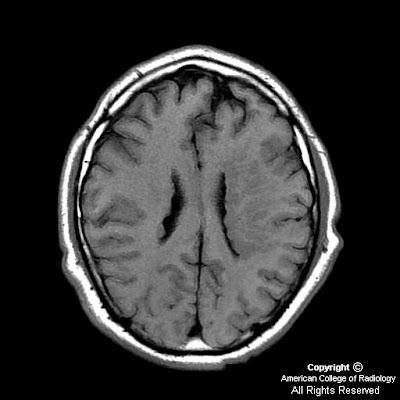

Within the medial subcortical portion of the anterior right temporal lobe, there is a 1.5 x 1.6 x 1.3 cm intraaxial lesion that demonstrates increased signal intensity on T2 and FLAIR images (Figure 2, 3, 5 and 6) and relatively low-signal intensity on T1-weighted images (Figure 1). The lesion has well-circumscribed and slightly-lobulated margins. No significant perilesional edema.

Postcontrast images do not reveal any appreciable enhancement (Figure 4 and 7).

This lesion appears to be located inferior and mostly anterior to the right amygdala, and expands the right parahippocampal gyrus medially and the right fusiform gyrus inferiorly.

Gangliogliomas are most commonly located in the superficial cerebral hemispheres, especially the temporal lobes. These tumors are usually firm, well-circumscribed masses and may expand the involved cortex. On CT, these have an appearance of low-density or cystic masses. Focal enhancement is seen in 50% of the cases and calcification in approximately 35%. MRI demonstrates these hemispheric lesions in a cortical location, being hyperintense on T2- and hypointense on T1-weighted images. Gadolinium enhancement is variable, often focal or nodular. PET typically shows decreased activity, indicating tumor hypometabolism. In children under 10 years, gangliogliomas can be larger and more cystic.